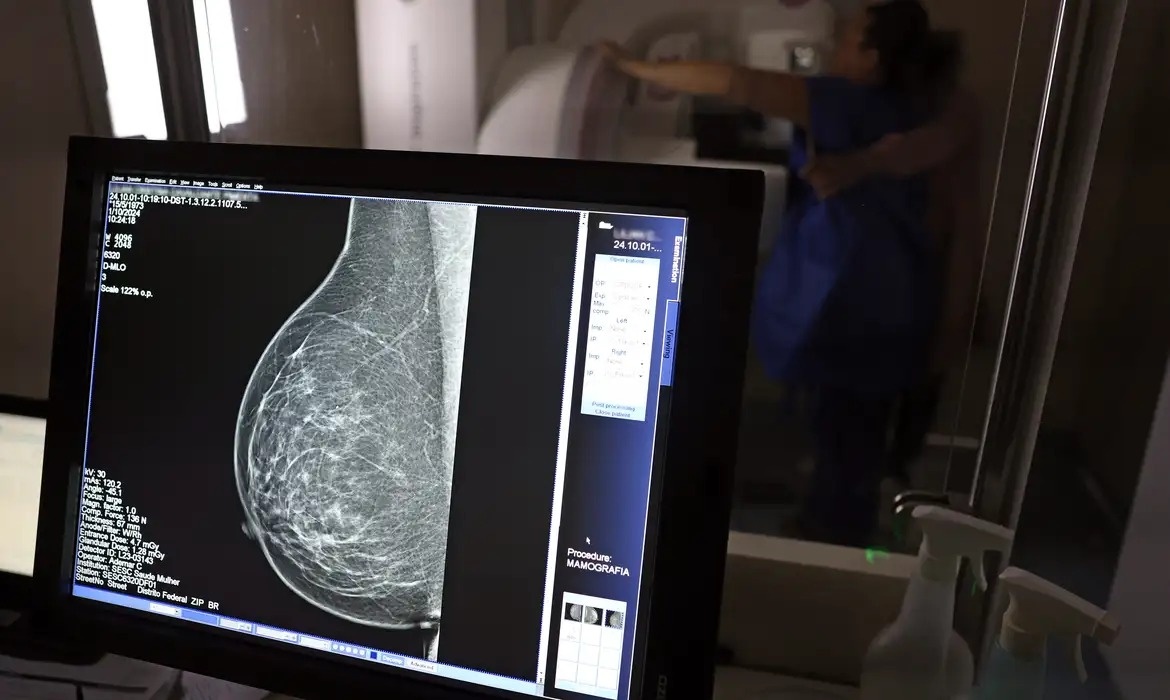

Governo Federal sanciona lei que amplia acesso das mulheres ao exame de mamografia fornecido pelo SUS

O presidente Luiz Inácio Lula da Silva sancionou a Lei nº 15.284, que fortalece o acesso à mamografia fornecida pelo Sistema Único de Saúde (SUS). Publicada nesta sexta-feira, 19, no Diário Oficial da União, a norma altera a Lei nº 11.664/2008 para ampliar a garantia do exame e determinar que seja oferecido a todas as mulheres a partir dos 40 anos, conforme diretrizes do Ministério da Saúde, com possibilidade de extensão para outras faixas etárias.

A lei garante a mamografia mesmo quando não há sinais ou sintomas de câncer. A faixa etária de 40 a 49 anos responde por 23% dos casos, e a detecção precoce aumenta as chances de cura. A paciente deverá ser orientada sobre os benefícios e as desvantagens do rastreamento, com a decisão tomada em conjunto com o profissional de saúde.

No ano de 2024, o SUS realizou aproximadamente 4 milhões de mamografias de rastreamento e 376,7 mil exames diagnósticos. Além disso, as mamografias em pacientes com menos de 50 anos representaram 30% do total — mais de 1 milhão de exames — mostrando a robusta cobertura do país e a importância do rastreamento e do diagnóstico precoce para salvar vidas.